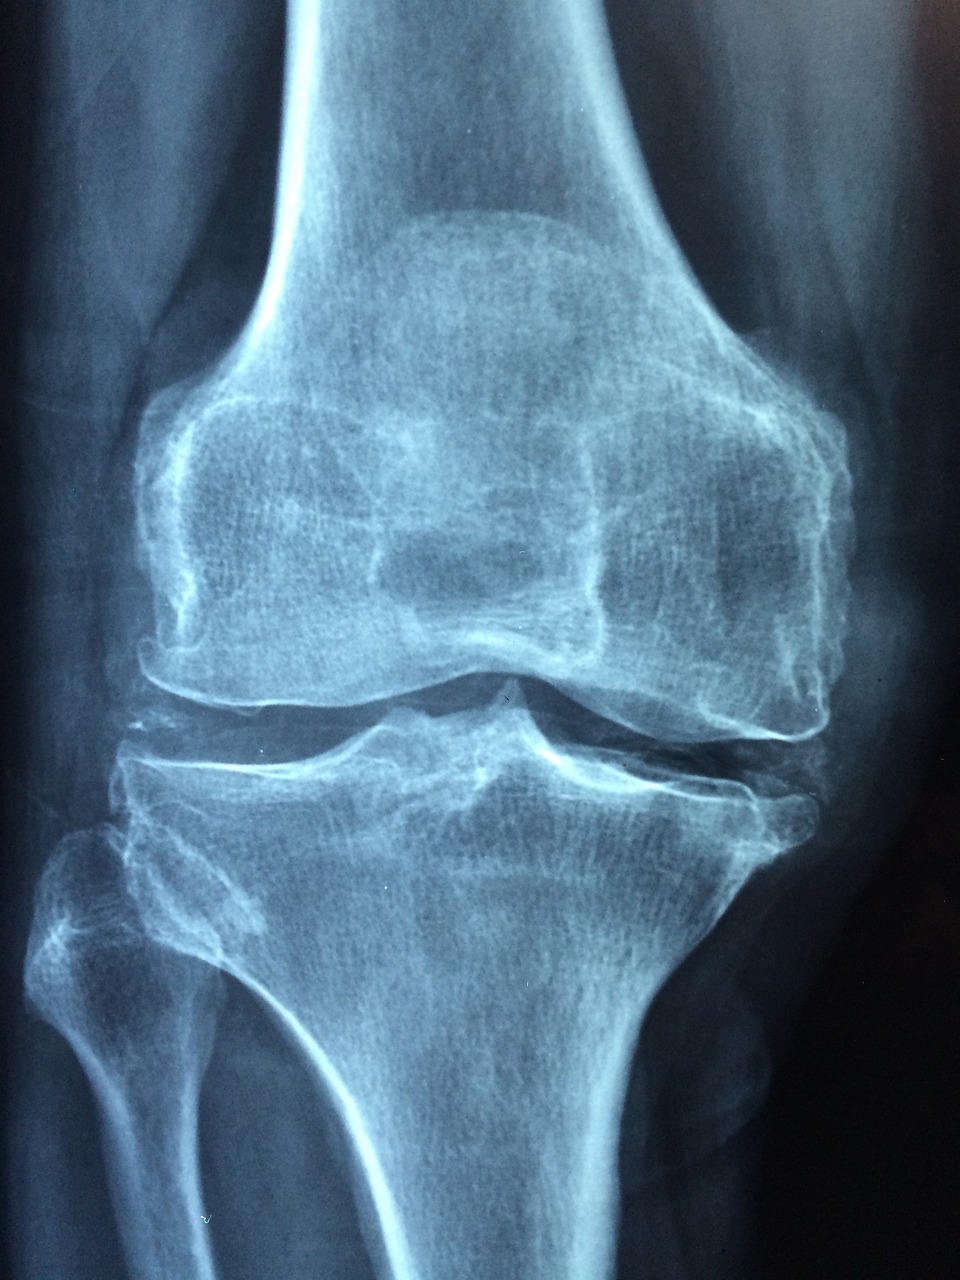

골다공증이란 뼈의 양이 감소하고 질적인 변화로 인해 뼈의 강도가 야해져서 골절이 일어날 가능성이 높은 상태를 말한다.

골다공증 검사비용은 검사 방법과 병원 위치 지역 등에 따라 달라지며, 일반적인 이중에너지 X선 흡수 계측법인 DXA 검사 비용은 5만 원~15만 원 사이이다. 이는 척추 (요추)와 대퇴골의 골밀도를 진단하는 방식이며, 통증이 없고, 방사선에 X선에 훨씬 적게 적게 노출되어 안전하게 골절의 위험성을 평가할 수 있는 방법이다. 검사 결과는 건강한 성인과 비교한 지표로 측정된 결과를 비교한다.